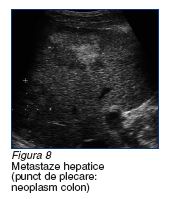

a. metastazele neoplasmului

colorectal sunt multiple (poate

exista si varianta unica!), relativ voluminoase (in circa 3/4

din cazuri au dimensiuni cuprinse intre 3 si 10 cm). Delimitarea tumorala prin halou

este intalnita

in circa 1/2 dintre cazuri,

iar cea neta,

doar in 1/5 dintre cazuri. Structura metastazelor recto-colice este in general neomogena, fara particularitati semnificative ale

ecourilor returnate. Exista o tendinta a metastazelor inalt diferentiate de a ajunge la dimensiuni mari

si de a dezvolta calcificari centrale, intratumorale (figura 8).